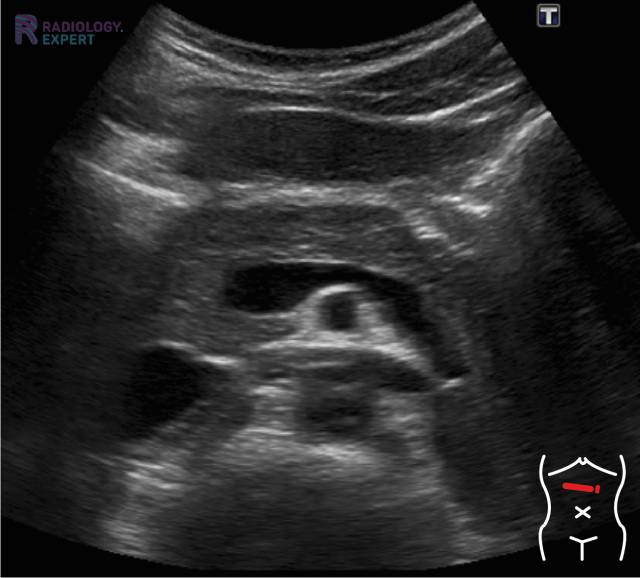

Echo onderzoek van een normaal pancreas in sagittale richting. Normale anatomie. Echo onderzoek van een normaal pancreas in sagittale richting. Normale anatomie.